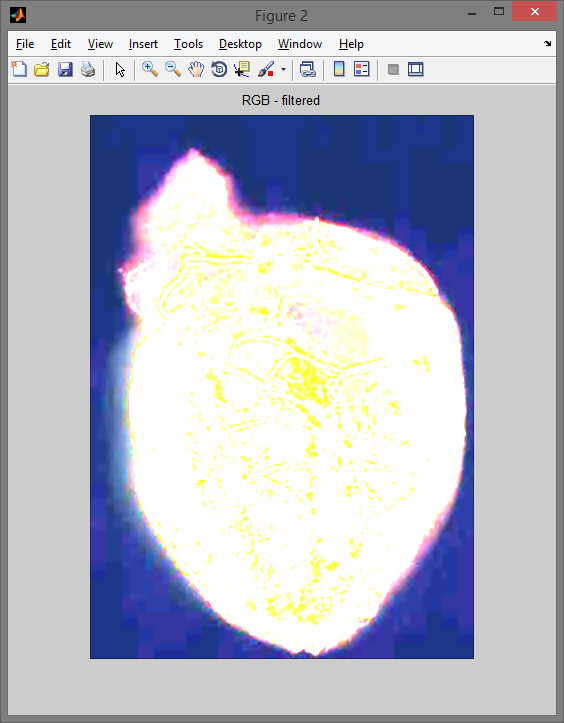

rgb_filtred = cat(3, red_filtred, green_filtred, blue_filtred);

figure,imshow(rgb_filtred); title('RGB - filtered');